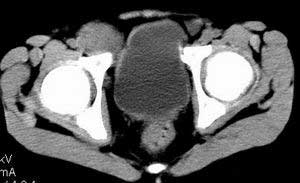

| 患者,男,9岁,因右下腹包块入院,血象不高,不规则发热,常超40度。 平扫: ![]() ![]() ![]() ![]() ![]() ![]() ![]() ![]() ![]() ![]() ![]() ![]() ![]() ![]() ![]() ![]() ![]() ![]() 增强: ![]() ![]() ![]() ![]() ![]() ![]() ![]() ![]() ![]() ![]() ![]() ![]() ![]() ![]() jiajie发言:骶椎右前区不规则软组织肿块,边缘光整,密度均匀,增强后均匀强化,右腹股沟区可见肿大淋巴结,临床有时发热,考虑淋巴瘤,儿童盆腔肿瘤应与神经母细胞瘤和横纹肌肉瘤鉴别。 longzhanghui发言:印象:盆腔右后壁不规则软组织肿块,并向前延伸.似为多个肿块融合,呈中等强化.初步考虑淋巴瘤. 听蝉观竹发言:右侧髂内、外组淋巴结肿大,从其形态和融合的情况看,同意大家意见-----考虑恶性病变,但是9岁男孩还要注意检查睾丸情况,有无隐睾? 常常类似情况是隐睾发生精原细胞瘤淋巴结转移,这个病例也要注意这一点!!! 广东凌发言:大家好,在这里我想说一下个人观点,我建议上传图片的同志能否辛苦一点就是把病史和图片都上传完整一点,比如这个病人的腹膜窗,并且这个病人的肠道的准备也是不怎么好,就从现有的质料看:病灶属于淋巴结肿大当无大的争议,有融合趋势,其内无坏死,边缘强化为主,故考虑:淋巴瘤!建议用腹膜窗看一下和肠道的关系! 阿圣发言:病灶属于淋巴结肿大当无大的争议,有融合趋势,其内无坏死,边缘强化为主,故考虑:淋巴瘤 结果是:淋巴瘤 病例来源:ct762。由宁静致远发布: http://www.radinet.com.cn/forum_view.asp?forum_id=4&view_id=2182 |